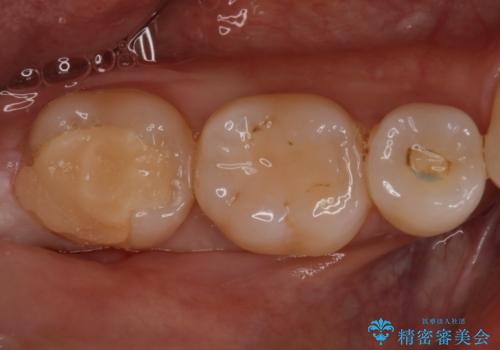

昔の被せ物が取れてしまった セラミックアンレーで治療

- 昔に治療した金属のかぶせものが取れてしまい来院されました。他院にて応急処置がされており、レントゲンなどで現状を把握した後、切削量が比較的少なく短期間で終了するセラミックアンレーにて治療いたしました。